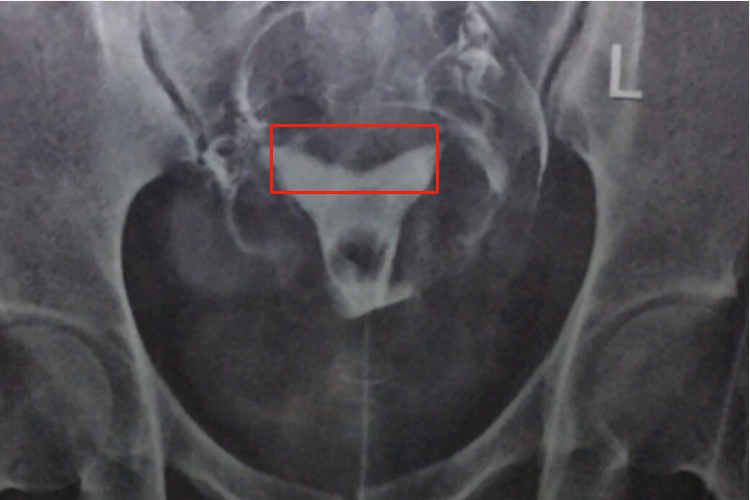

马鞍形子宫临床称为鞍形子宫,轻度鞍形子宫的造影见子宫底凹陷,犹如鞍状。

马鞍形子宫临床称为鞍形子宫,轻度鞍形子宫的造影见子宫底部稍向下凹陷,犹如鞍状。患者在未妊娠时一般无临床症状,妊娠后可能会出现流产或者早产等症状。